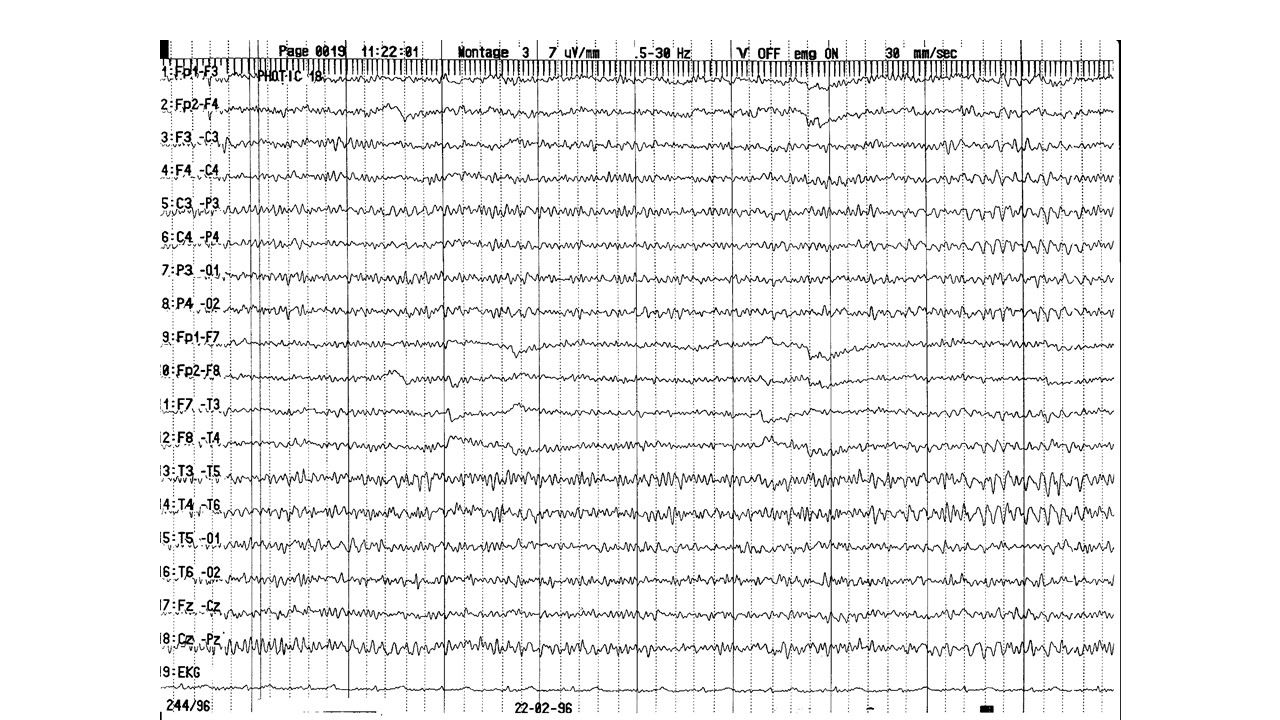

folie560.jpg